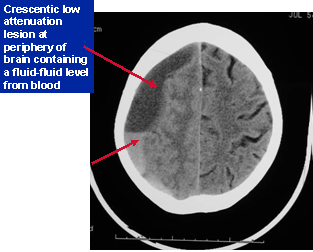

Subdural hematoma